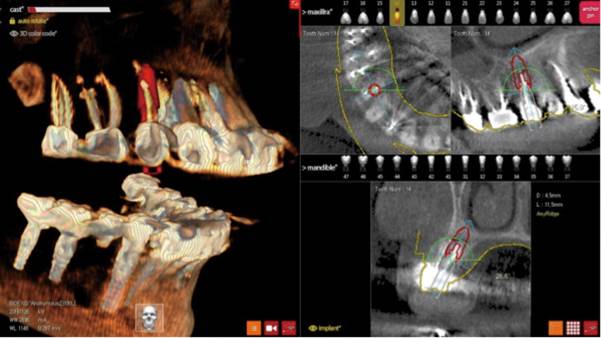

Clinical case: Digital Data Save concept in upper jaw premolar area

- Courtesy of Dr. Lysov Alexander Dmitrievich & Dr. Sofronov Matvey Vitalievich, Russia -

AnyRidge, R2GATE, R2GATE guide, ISQ value, initial stability, immediate loading, KnifeThread, maxillary posterior, #14, Digital, Dr. Lysov Alexander Dmitrievich, Dr. Sofronov Matvey Vitalievich, zirconia abutment, CAD/CAM crown

“AnyRidge & R2GATE show stable results

after immediate extraction, immediate implant placement, & immediate loading,

even with low bone density.”